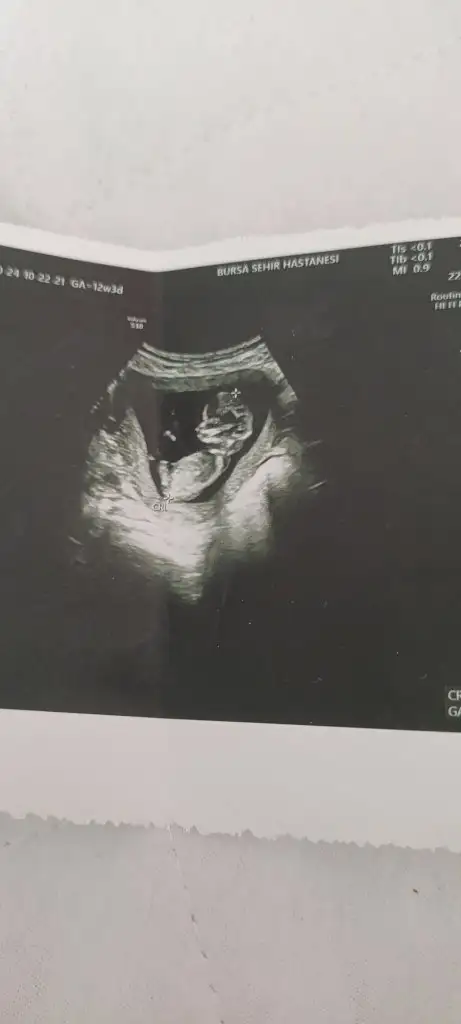

Kızzkızlarrr son kez cinsiyet tahmini yapabilir misinizzz

doktor yüzde 80-90 bir tahminim var dedi ama tam cinsiyeti göremedisizceee teyzeleriii

Banada bakarmisiniz ultrason resmim uste kaldi

Bebek gelişirken cinsel organında bir açı oluşur orada da bir açı var açı dikeyse erkek yatay ise kızdır oradaki açı biraz yatay sizin nub teorisi. Benim kızımda da tutmuştu bu teorineye göre tahmin ettiniz acaba içimde bir umut oluştu

Daha cok kücük ama teorilere göre falan tahmin yürütebilirmisinz öık merak ediyormKızlar bana da bakarmısınzEki Görüntüle 3501687

Kızlarım merhaba benim dee 13+2 cinsiyet tahmininizi alabilir miyim